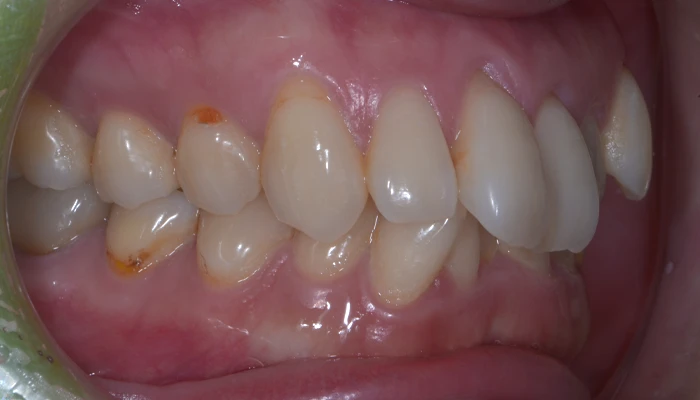

治療例18. 八重歯を治したい

治療前

治療後

主訴 | 八重歯を治したい |

---|---|

治療期間 | 10ヶ月 |

治療費 | 70万+tax (別途調整料) |

治療内容 | インビザライン矯正(マウスピース矯正) |

治療のリスク | 後戻り |